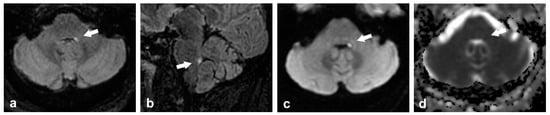

| Neurological Disorder | Alterations | CNS Atrophy Pattern | References |

|---|---|---|---|

| FXTAS | Reduced FA in all CPs Reduced width of the MCP MCP sign | Generalized brain and cerebellar atrophy | [8,15,33,34,36,37,40] |

| Joubert’s syndrome | Absence of decussation of the SCP tracts Elongation, horizontalization, and increased width of the SCP, forming the molar tooth sign | Not applied (hypo-dysplasia of the cerebellar vermis) | [91] |

| MSA (MSA-C variant) | Reduced width of the SCP and MCP Reduced FA in the MCP Pontine cruciform hyperintensities (hot cross bun sign) MCP sign T2 hyperintensity of the ICP (ICP sign) | Brainstem Cerebellum | [92,94,95,107] |

| Progressive supranuclear palsy | Reduced FA and reduced width of the SCP | Midbrain | [3] |

| Spinocerebellar ataxia | Reduced FA in all CPs Reduced width of the MCP Hot cross bun sign MCP sign | Pons Cerebellum | [2,14,96,97,107] |

| CARASIL | Symmetrical T2/FLAIR hyperintense signal in the MCP connecting through the pons (arc sign) | Brain Brainstem Cerebellum | [10] |

| CLIPPERS | MRI punctate Pattern of patchy gadolinium enhancement ‘peppering’ the brainstem and MCP | Not characteristic at early stages | [98] |

| Diffuse axonal injury | Reduced FA in all CPs Subtle hyperintense small lesions on T2 weighted image and/or hypointense on T2*-weighted image 1 (microbleeds) | Not characteristic at early stages | [99] |